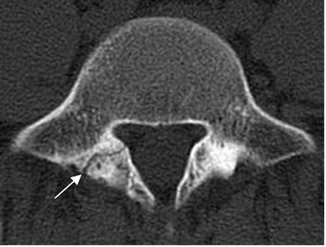

Se aprecia como imagen radiolúcida en la pars interarticular, con esclerosis de los fragmentos, mejor visto en una Rx oblicua. Puede ser uni o bilateral. En la TAC se encuentran los mismos hallazgos, en cortes por encima del nivel del disco. (1). (Fig 72 a 74).

Fig 72. Listesis.

TAC axial. Solución de continuidad en la lámina derecha, por listesis unilateral.